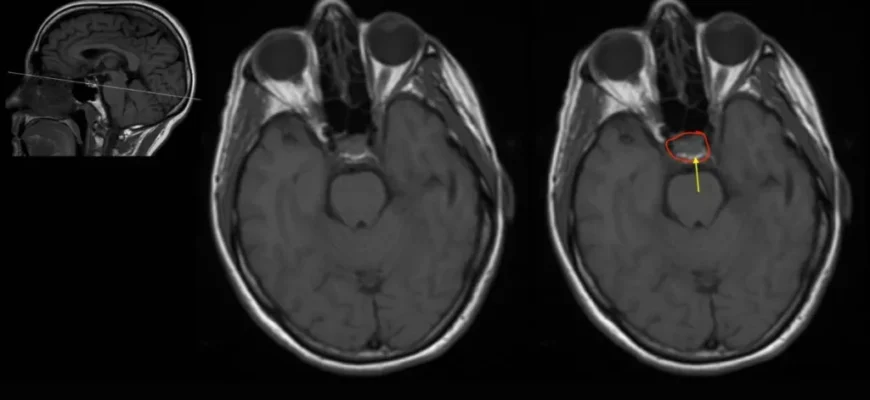

Діагностика: як виявити невидиме?

Ось тут починається найцікавіше. Як же побачити те, чого не можна видимим поглядом уздріти? Розв’язка такого питання на плечах сучасної медицини. Потрібно комплексно підходити до діагностики, використовувати магнітно-резонансну томографію (МРТ) або комп’ютерну томографію (КТ). Методики, які вже не ноу-хау, а пройдені етапи діагностичного арсеналу, що дозволяють виявити зміни коркових структур.